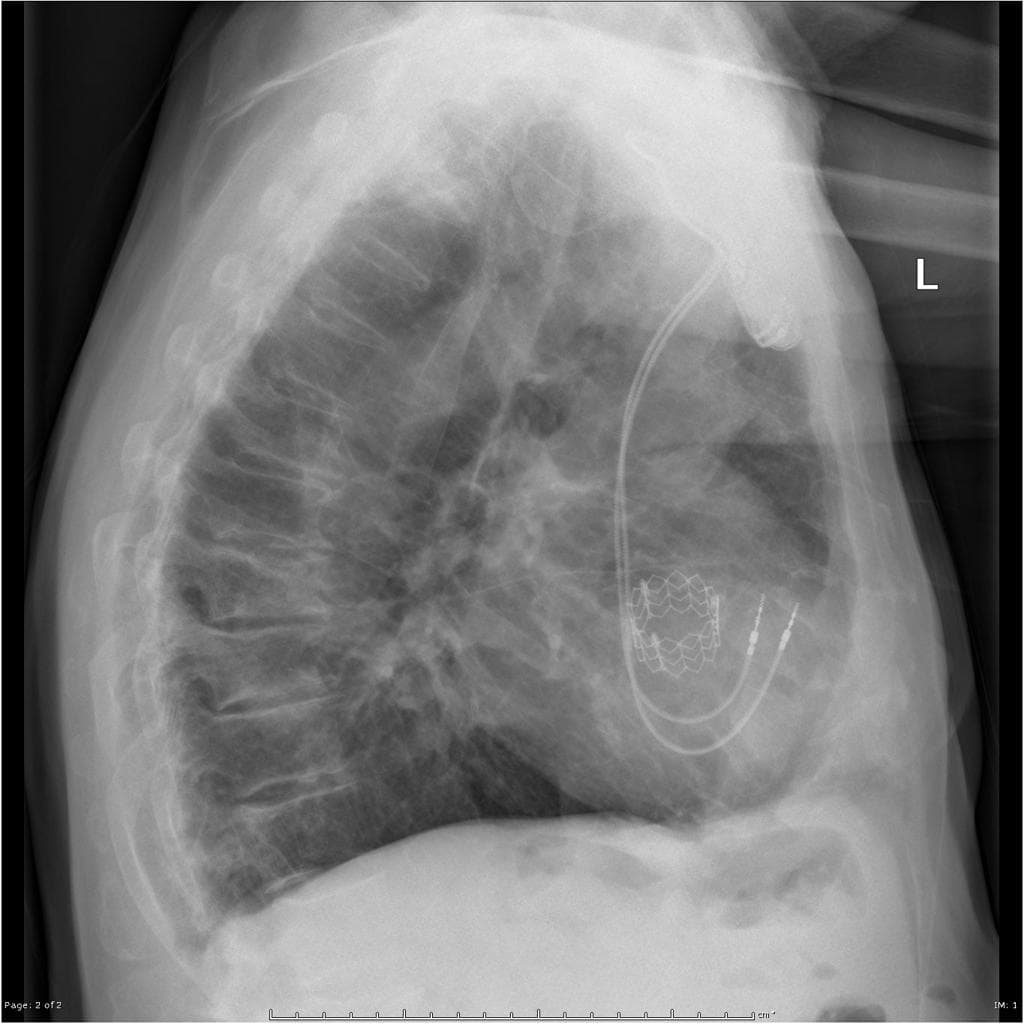

Lateral

X-ray•Lateral•1 Img

- Stent kim loại (metallic stent) tại vị trí của van động mạch chủ (aortic valve) và động mạch chủ lên (ascending aorta).

- Quan sát rõ nhất trên phim nghiêng (lateral view).

THẢO LUẬN (DISCUSSION): Sau khi chọc động mạch đùi (femoral arterial puncture), van động mạch chủ (aortic valve) ban đầu được nong bằng bóng (balloon dilated), sau đó một stent có thể giãn nở (expandable stent) được đặt xuyên qua vòng van (annulus), bên trong chứa các lá van nhân tạo (artificial internal valve leaflets).

- "Trên hình ảnh, thiết bị thường nằm ở vòng van động mạch chủ và được quan sát rõ nhất trên phim X-quang ngực nghiêng."

Thay van động mạch chủ qua ống thông (TAVR), còn được gọi là TAVI, là một thủ thuật được sử dụng để điều trị hẹp van động mạch chủ nặng có triệu chứng, đặc biệt ở những bệnh nhân có nguy cơ trung bình đến cao khi phẫu thuật tim hở. Thủ thuật thường bao gồm tiếp cận qua động mạch đùi, sau đó là tạo hình van bằng bóng đối với van tự nhiên. Một van bằng vật liệu sinh học có thể thu nhỏ (thường là màng tim bò hoặc lợn) gắn trên một stent kim loại sau đó được triển khai xuyên qua vòng van. Trên hình ảnh X-quang, stent xuất hiện dưới dạng cấu trúc hình trụ cản quang tại vị trí van động mạch chủ, dễ dàng nhận diện trên phim nghiêng hơn so với phim thẳng.